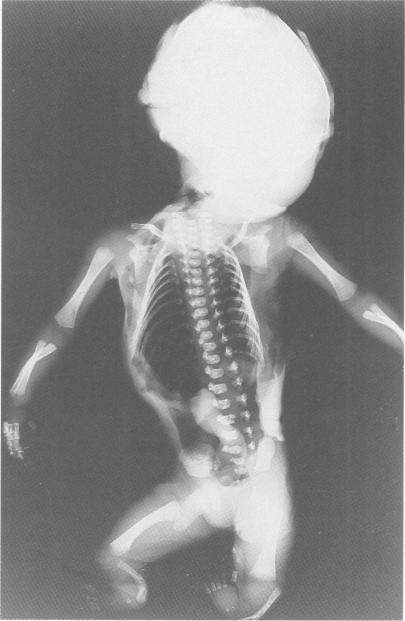

Absence/hypoplasia of tibia, polydactyly, retrocerebellar arachnoid cyst, and other anomalies: an autosomal recessive disorder.

Absence or hypoplasia of the tibia has been reported to occur as an isolated hereditary malformation as well as a feature of several autosomal recessive and autosomal dominant syndromes. We report three sibs with absence or hypoplasia of the tibia in association with other malformations whose parents are first cousins once removed. These infants appear to have a "new" autosomal recessive syndrome.